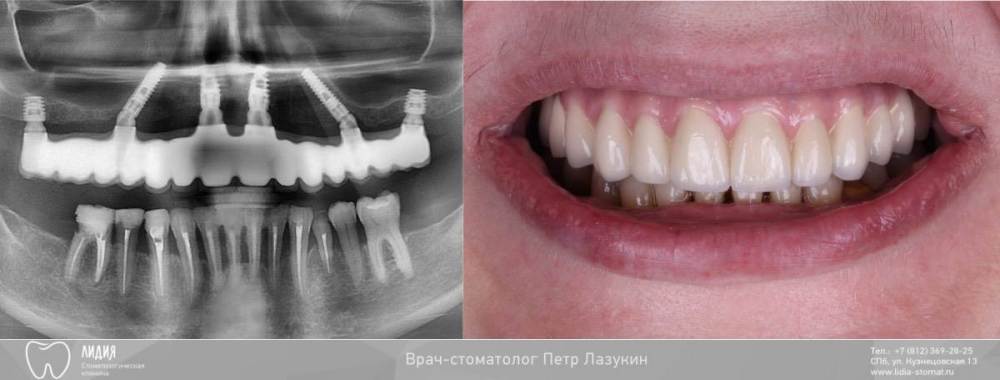

pit Опубликовано 2 августа, 2022 Поделиться Опубликовано 2 августа, 2022 Клинический случай протезирования верхней челюсти с опорой на имплантаты. Пациент обратился с жалобами на подвижность зубов, постоянное воспаление десен. Многократно проходил лечение у пародонтолога, им же был направлен ко мне. На момент осмотра глубина зондирования до 9 мм. Зубы шинированы, подвижны вместе с шиной. Ситуацию сильно осложняла открытая улыбка с визуализацией 3-х мм десны и эстетические пожелания пациента. Предложены 2 плана лечения. 1. Все на 6-и и 14 коронок. 2. Все на четырех и 12 коронок Выбран первый вариант. Лечение проведено в 2 этапа 1. Удаления, редукция гребня, установка имплантатов Hi-Tec. В позициях 15 и 25 зубов под углом, в позиции 17и 27 коротыши. Подсажены ССТ с обоих бугров верхней челюсти. Установка мультиюнит абатментов, армированные временные коронки. 2. Через 4 месяца постоянные МК коронки. 5 2 1 Ссылка на комментарий